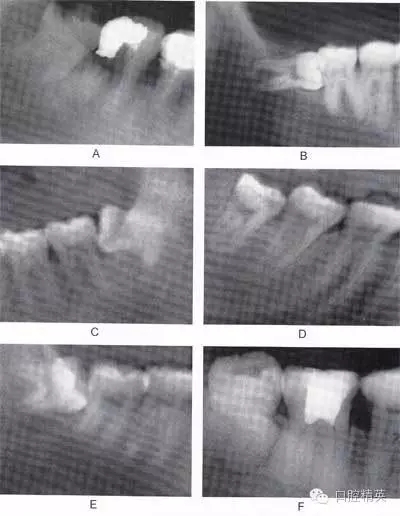

圖6-2 根據(jù)阻生牙相對于下頜升支前緣位置關(guān)系分為:第1類 (圖A):下頜升支前緣和第二磨牙遠(yuǎn)中面之間有足夠的間隙容 納第三磨牙牙冠;第2類(圖B):約一半的第三磨牙牙冠被下 頜升支前緣覆蓋;第3類(圖C):第三磨牙全部位于下頜升支 前緣內(nèi)

A

B

C

圖6-3 相對于聆平面的位置關(guān)系分為:A分類(圖A):第三磨牙殆面平齊于第二磨牙聆面;B分類(圖B):第三磨牙(牙合)面 位于第二磨牙殆面和牙頸部平面之間;C分類(圖C):第三磨牙(牙合)面低于第二磨牙的牙頸部平面。一般情況下,近中阻生拔除難度比垂直阻生小,垂直阻生比水平阻生小,水平阻生比遠(yuǎn) 中阻生小;第1類比第2類簡單,第2類比第3類簡單;A分類比B分類簡單,B分類比C分類簡單。另外拔牙難度與牙齒形態(tài)、 患者年齡、牙周骨質(zhì)密度以及與下牙槽神經(jīng)管的關(guān)系也有關(guān)聯(lián)。 骨質(zhì)密度越大,年齡越大,患牙牙周骨質(zhì)鈣化程度越高,越難拔除.

圖6-4 以上類型的下頜第三磨牙由于根阻力大,一般需要分根才能拔除

A.多根牙 B。超長根 C。牙根向遠(yuǎn)中彎曲 D。兩根環(huán)抱 E。根分叉大 F,根端肥大 G。彎根 H.U型根(X線片及離體牙)

圖6-5 以上類型的下頜第三磨牙由于根阻力小,一般不需分根,即可拔除。

A.合并根 B.短根 C.椎形根 D.牙根向遠(yuǎn)中彎曲 E.根分叉小 F.根尖未完全形成